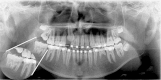

Fusion or gemination? An unusual mandibular second molar

Fusion and gemination is not an uncommon finding and affected most primary dentition and the permanent maxillary incisors. These changes can develop a series of complication. A 11-year-old male presented radiography finding: an unusual mandibular second molar. A well-documented case brings a challenge for radiologists classify between fusion and gemination. In conclusion, this alteration although common in other regions, there are no case in the literature involving "second and third" molar.